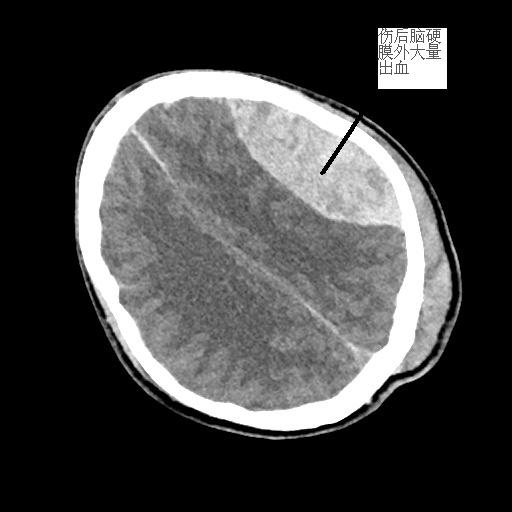

患者潘先生,因騎車摔倒入院搶救。入院時(shí),潘先生神志已模糊,無法對(duì)答,檢查檢驗(yàn)提示顱內(nèi)多發(fā)損傷,出現(xiàn)腦疝,病情危重,我院神經(jīng)外科團(tuán)隊(duì)緊急聯(lián)系福醫(yī)大附二院當(dāng)日值班專家來院開展開顱手術(shù)。經(jīng)及時(shí)搶救,患者病情穩(wěn)定,轉(zhuǎn)危為安。

<<<< 治療前后對(duì)比